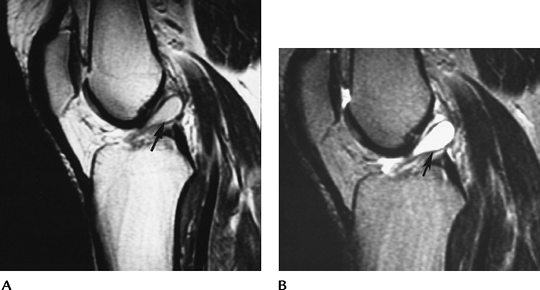

FIGURE 5-36 PCL tear. Sagittal proton-density (A) and T2-weighted (B) images demonstrate thickening and increased signal intensity in the PCL with avulsion from the tibial attachment (arrow).